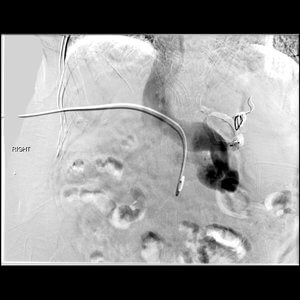

50 year old female patient s/p liver transplant presents with persistent encephalopathy. A massively dilated splenorenal shunt was identified but an attempted BRTO procedure failed. The patient presents for transhepatic embolization.

Comment: This patient had gradually progressing and increasingly severe and prolonged episodes of encephalopathy after liver transplantation. As it turns out, there was a significant splenorenal shunt that was likely responsible for this. An attempt was made at an outside hospital to perform retrograde embolization via the left renal vein but the large size of the varices made that ineffective. As a result, we attempted to access the splenorenal shunt using a transhepatic approach. Once the portal vein was catheterized, a venogram demonstrated hepatofugal flow with preferential flow into the splenorenal shunt. We were then able to catheterize the shunt and embolize the major branches. Following embolization, hepatopetal flow was restored.